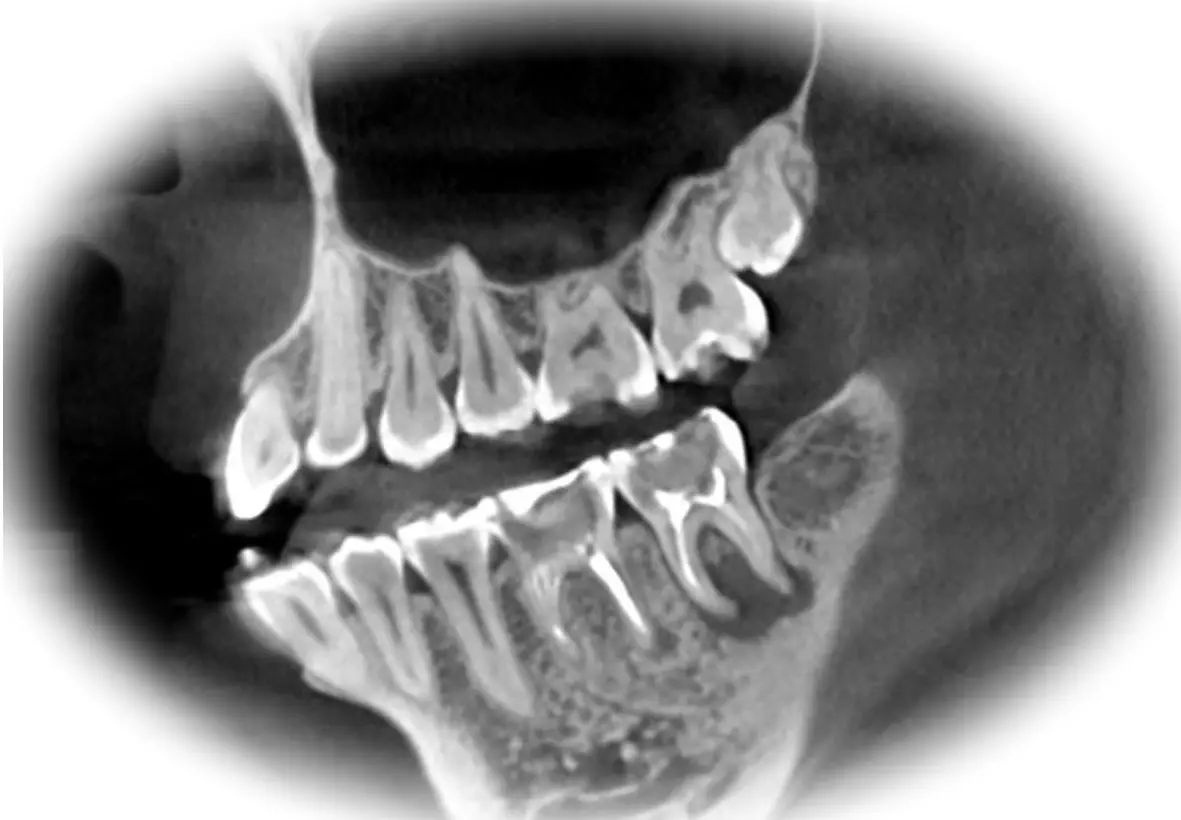

Проведение компьютерной томографии базируется на принципе пропускной способности рентгеновских лучей. Коническое излучение многоразово охватывает голову пациента, что позволяет сократить время обследования и уменьшает дозу вредного излучения. Если взять для сравнения классическую рентгенологическую диагностику, данный метод позволяет более детально визуализировать различные структуры организма: мышцы, кости, полости.

Главная особенность томографа заключается в том, что он может выполнять серию снимков, на основании которых формируется 3D модель объектов исследования. Изображения, полученные методом 3D-томографии, очень точные, и стоматолог может изучать их в различных проекциях, добавлять нужные фильтры, чтобы точно визуализировать самые мелкие детали всех анатомических структур челюсти. Специально созданное для такой диагностики программное обеспечение генерирует результат с помощью «искусственного интеллекта» – подбора соответствующего диагноза из базы загруженных изображений.